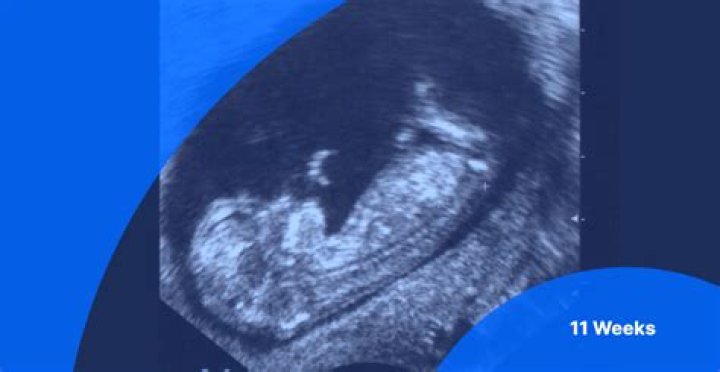

An 11 week ultrasound gender prediction is sometimes an option, but it could be wise to wait until your second scan when it will be more accurate. At this stage, your baby’s head will appear quite large with a small body. They are developing tiny fingernails, ears, and even hair.

And by week 11 of pregnancy, baby has other distinct human characteristics: hands and feet in front of his body, ears nearly in their final shape, open nasal passages on the tip of his tiny nose, a tongue and palate in the mouth, and visible nipples.